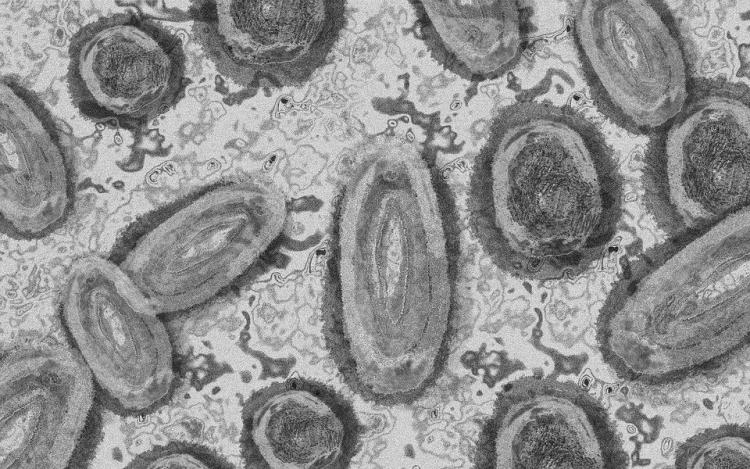

Megfertőződött majomhimlővel egy négyéves kislány Németországban - jelentették kedden német hírportálok az országos közegészségügyi intézet (RKI) adatai alapján.

Németországban első alkalommal mutatták ki a kórokozót gyermek szervezetében.

A kislány két fertőzött felnőttel él együtt a Baden-Württemberg tartományi Pforzheimben. A tartományi egészségügyi minisztérium tájékoztatása szerint elővigyázatosságból vizsgálták meg, miután kimutatták az első fertőzést a háztartásban. Eddig nem jelentkeztek nála a betegség tünetei.

Az RKI-nál május elején regisztrálták az első németországi majomhimlős eseteket. Keddig 2982 igazolt fertőződést jegyeztek fel. A betegség mind a 16 tartományban megjelent.

Az intézet ismeretei szerint a vírus elsősorban szexuális úton terjed Németországban, főleg férfiak körében. A fertőzöttek szinte mind felnőtt férfiak, csupán hét nő és két kiskorú - egy 15 és egy 17 éves kamasz - van közöttük.

Az esetek többségében a fertőzés enyhe lefolyású betegséggel jár. Halálos áldozatot Németországban még nem regisztráltak.

Az Afrika egyes részein évtizedek óta ismert és ritkán előforduló majomhimlő május óta Európában, Észak-Afrikában és más térségekben is terjed. Az Egészségügyi Világszervezet (WHO) júliusban globális egészségügyi vészhelyzetnek nyilvánította a járványt.